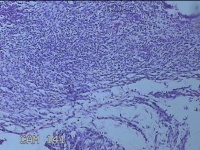

左卵巢囊肿

性别

女

年龄

32岁

临床诊断

左卵巢巧克力囊肿破裂

一般病史

下腹疼痛2天,加重10小时。

标本名称

大体所见

灰白暗红色囊壁样组织5.3x2x1.3cm一堆,表面糜烂,因已切开,囊内容物已流失,囊壁厚0.1cm。

图2